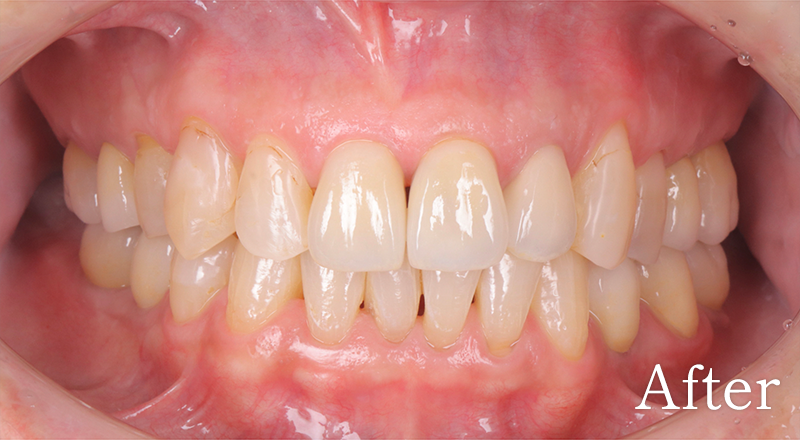

骨格2級患者に対し、審美と機能の両立を図り治療を行なった1症例

主訴 右上のブリッジがよく外れる

治療内容 上犬歯インプラント、GBR、咬合再構成、上顎前歯部歯冠長延長術、セラミック治療

治療期間 約2年

費用 診断料:22万円(税込)

右上犬歯インプラント埋入手術:27.5万円(税込)

GBR:11万円(税込)

セラミック補綴:22万円(税込)

セラミック治療:11万円(税込)×18本